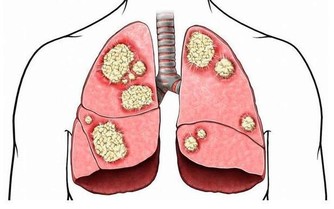

第三名:偏方、保健品在台灣慢性腎病發病率很高,可能和當地人愛吃偏方、保健葯有關。

一些所謂〝補充蛋白粉,提高抵抗力〞的保健品很可能導致蛋白質攝入過多,給腎臟帶來負擔。

第七名:吃得過咸、吃高嘌呤涮菜冬天,人們都喜歡吃火鍋,但涮肉吃多了也會傷腎。

涮菜中如豆製品等是高嘌呤食物,而且涮肉的湯汁中嘌呤含量很高,

這些都會造成脾胃負擔過重,也會加重腎臟負擔。

高嘌呤、高脂肪、高熱量食物攝取過多,時間長了,再好的腎臟都會累。

其實,平時吃得太咸、太甜、太油,蛋白質吃得太多都會加重腎臟的負擔。